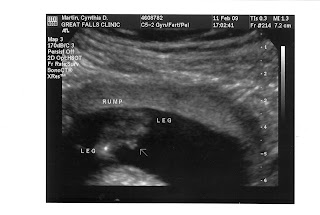

more ultasound pics